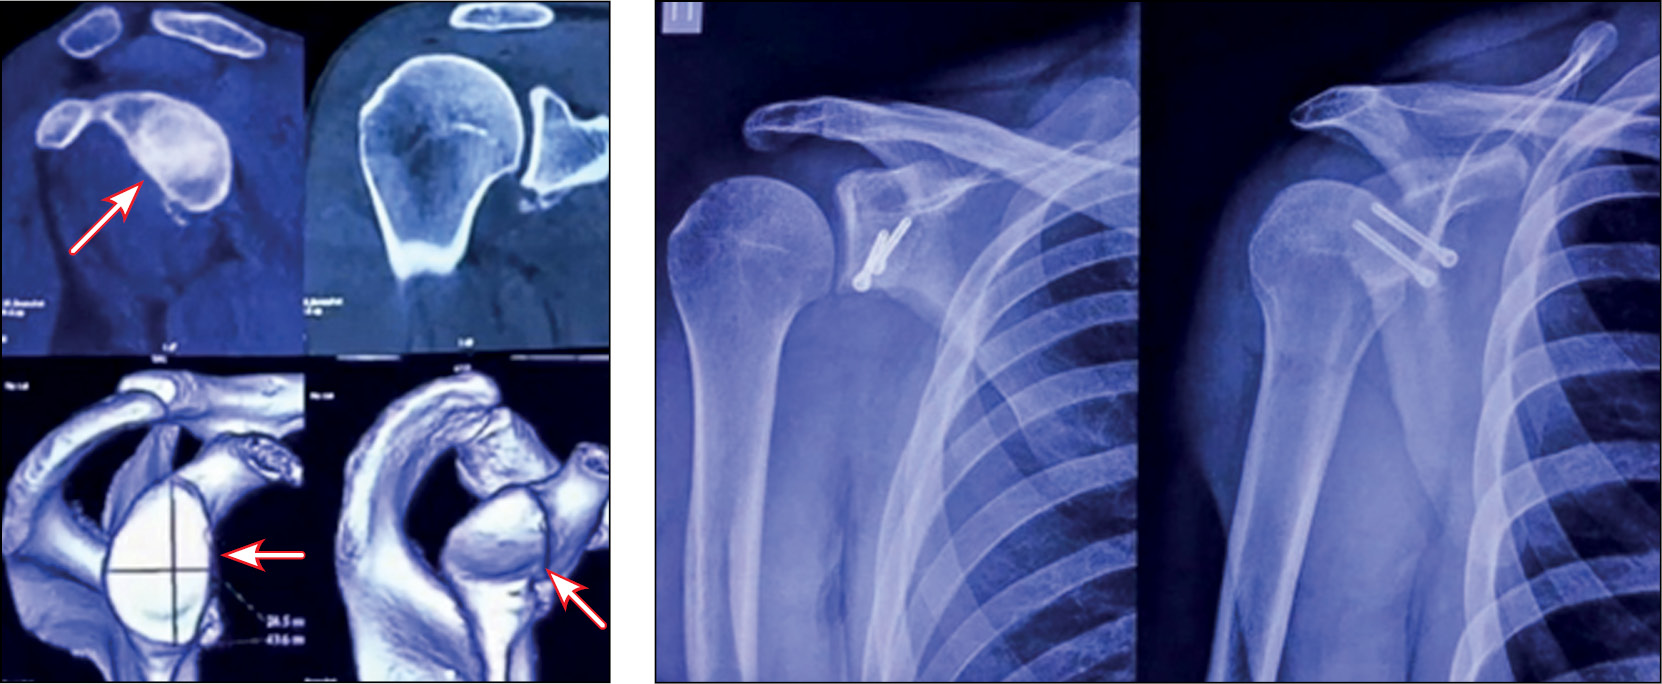

Пациент Н., 27 лет, с рецидивирующей нестабильностью левого плечевого сустава (заслуженный мастер спорта по спортивной гимнастике).

В 2022 году выполнена артроскопическая стабилизация с использованием свободного костного аутотранс-плантата правого плечевого сустава (рис. 15).

Рис. 15. Рентгенография правого плечевого сустава: а — до операции, b — через 6 месяцев после неё.

Fig. 15. X-ray of the right shoulder joint: a — before surgery, b — 6 months after it.

Положение костного аутотрансплантата через 6 мес после операции. Тестирование функционального состояния мышц через 6 месяцев после операции для оценки спектральной мощности на левой руке (рис. 16–18).